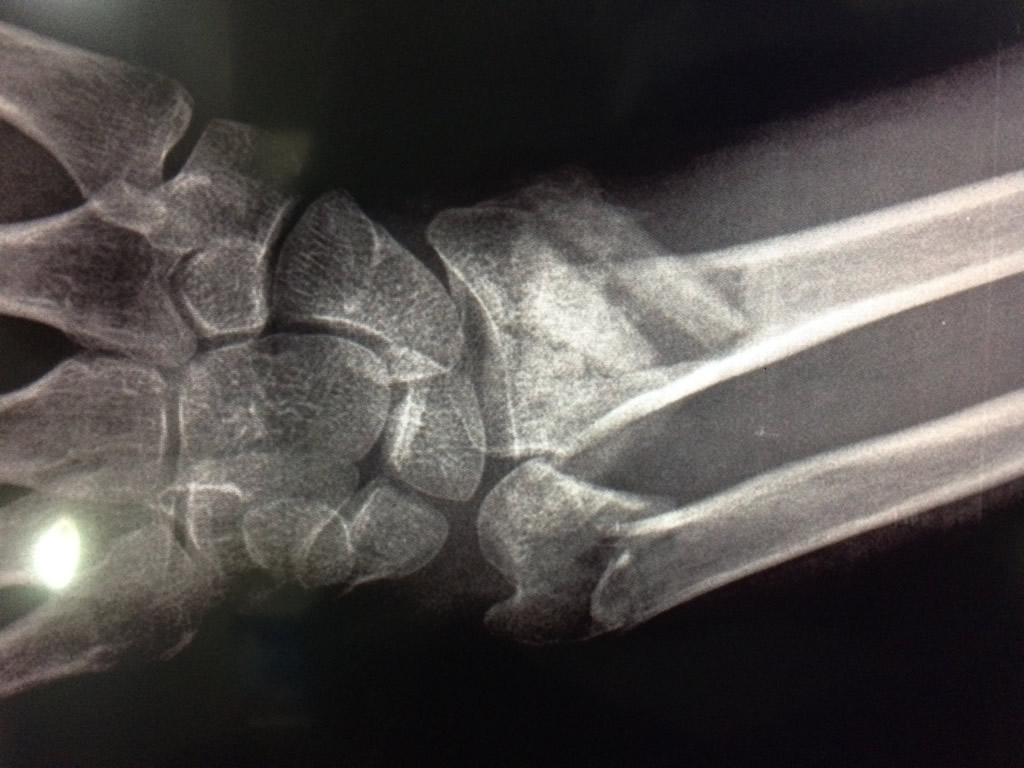

Cirugía de Fémur - Cirugías de Muñecas y Manos

Los procedimientos más comunes en cirugía de la mano son aquellos destinados a reparar traumatismos, incluyendo lesiones de tendones, nervios, vasos sanguíneos, y articulaciones; huesos fracturados; y quemaduras, cortes, y otros daños de la piel.